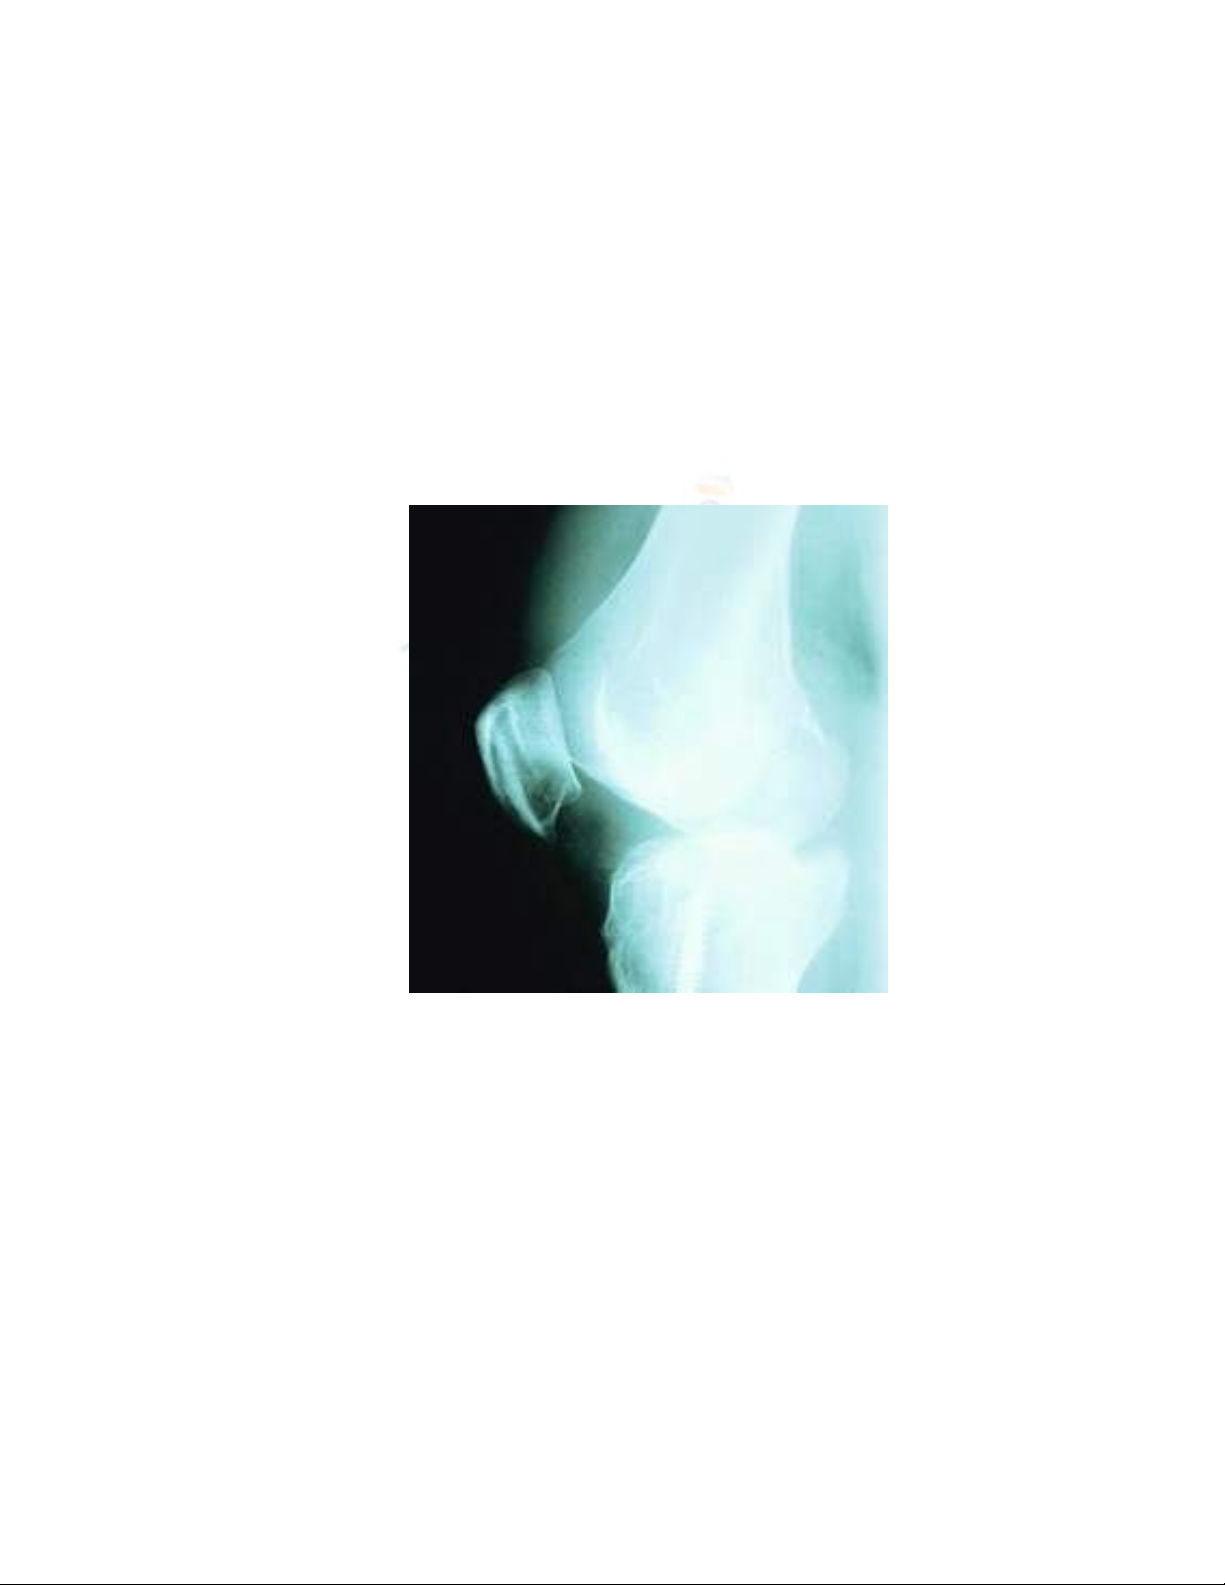

liệt, tuyến giáp và phế quản-phổi. Hình ảnh di căn xương thường gặp là hủy xương

ngoài ra gặp ít hơn hình ảnh đậm đặc xương hoặc hình ảnh hỗn hợp. Cột sống là